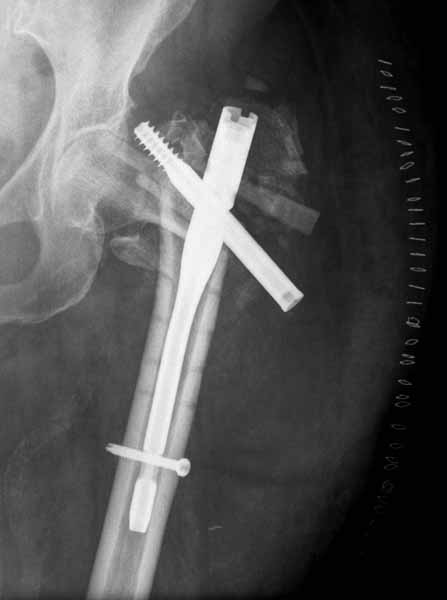

Среднестатистическая старушка, которых много. Сопутствующие болезни, ходила с палочкой. Готовили к операциям как обычно. По поводу этики - может замечание и правильное. Было бы мое - сказал. Думаю это здесь не главное. Главное - избегать подобных ситуаций. В своей практике не припомню cutout DHS.Возможно работает calcar. Для многих evidence based TAD - Tip to Apex Distance. Но если проводить через calcar, то TAD может быть больше 25 мм.

Думаю, что гвоздь или DHS - надо ставить через calcar. Логично, что на прочном месте будет меньше cutout. Да и дорожка для cutout в этом случае длиннее.